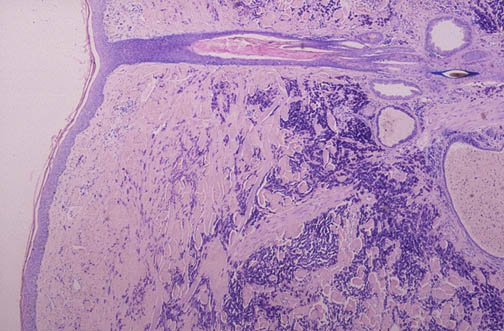

| A giemsa stain demonstrates numerous mast cells in the dermis in this case of urticaria pigmentosa, which is a form of localized mastocytosis seen most often in children. Lesions are often in groups, or may be solitary, and appear as brown pruritic papules. The mast cells contain numerous purple granules; the granules contain many substances, including vasoactive amines such as histamine, which are released upon activation and degranulation of the mast cells to cause the symptoms. A medium power view is seen below. |